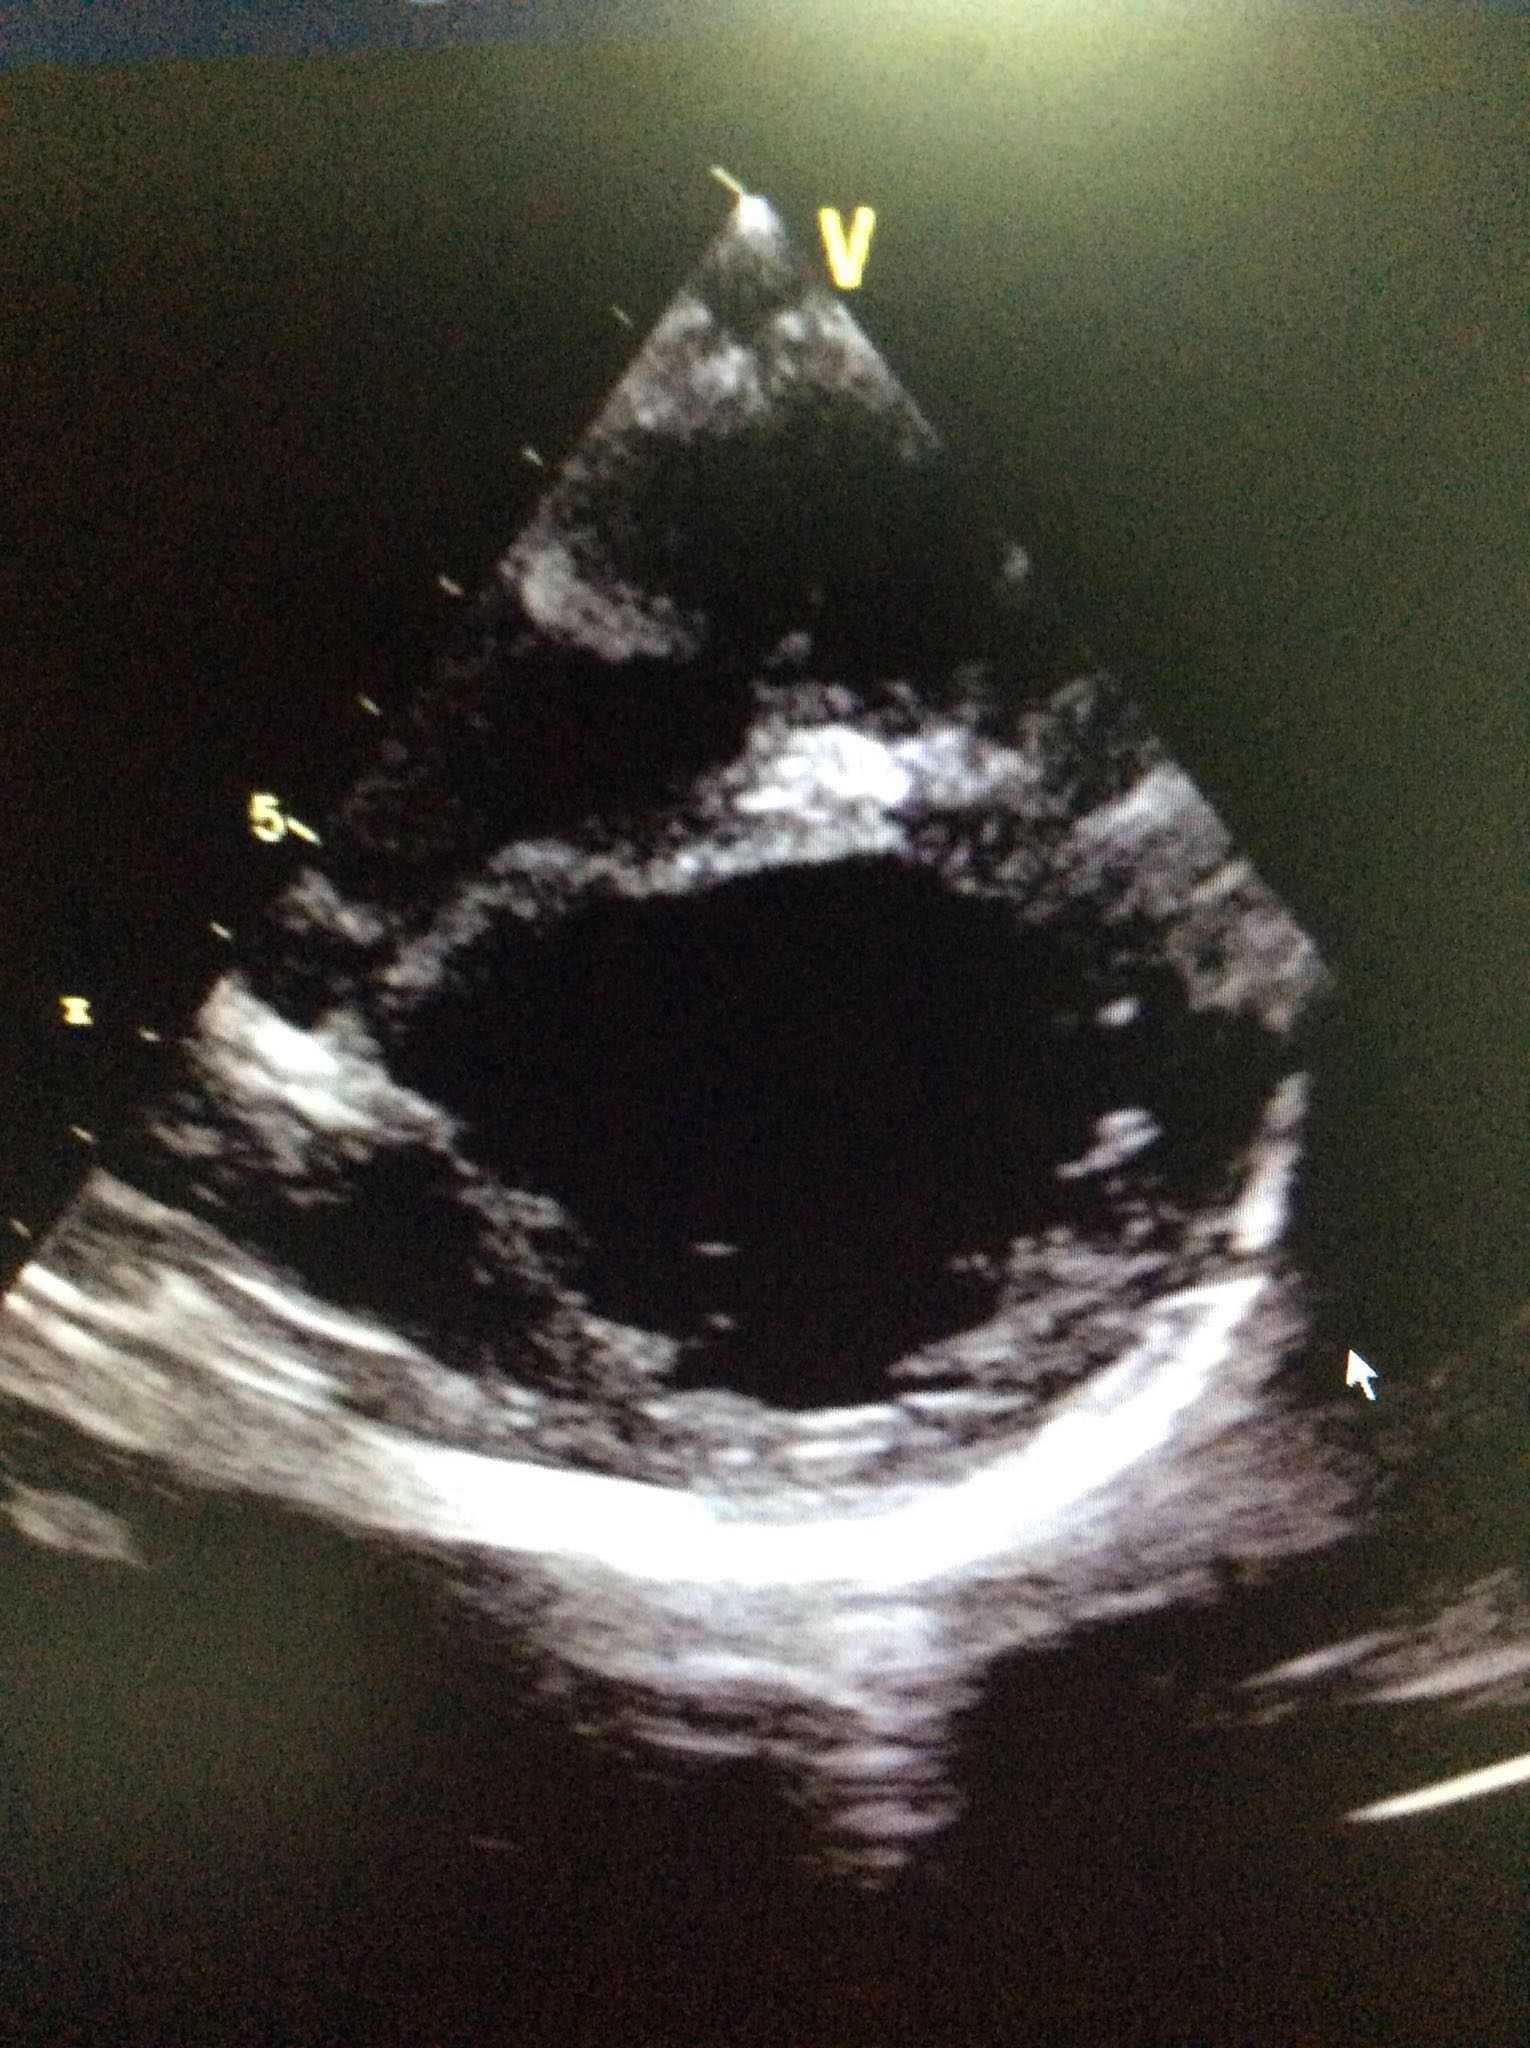

查体:心界增大,心音尚有力,肝脏肋下4cm,脾脏未触及。 心脏超声:全心长大,心机致密化不全,EF40%。心电图:窦性心律,异常Q波。

诊断:心肌致密化不全 进一步完善CTA未见冠脉起源异常,心脏MRI尚未回示。予地高辛强心,卡托普利改善心是重构,利尿,保心等治疗。患儿一般情况可,目前仍在治疗中。